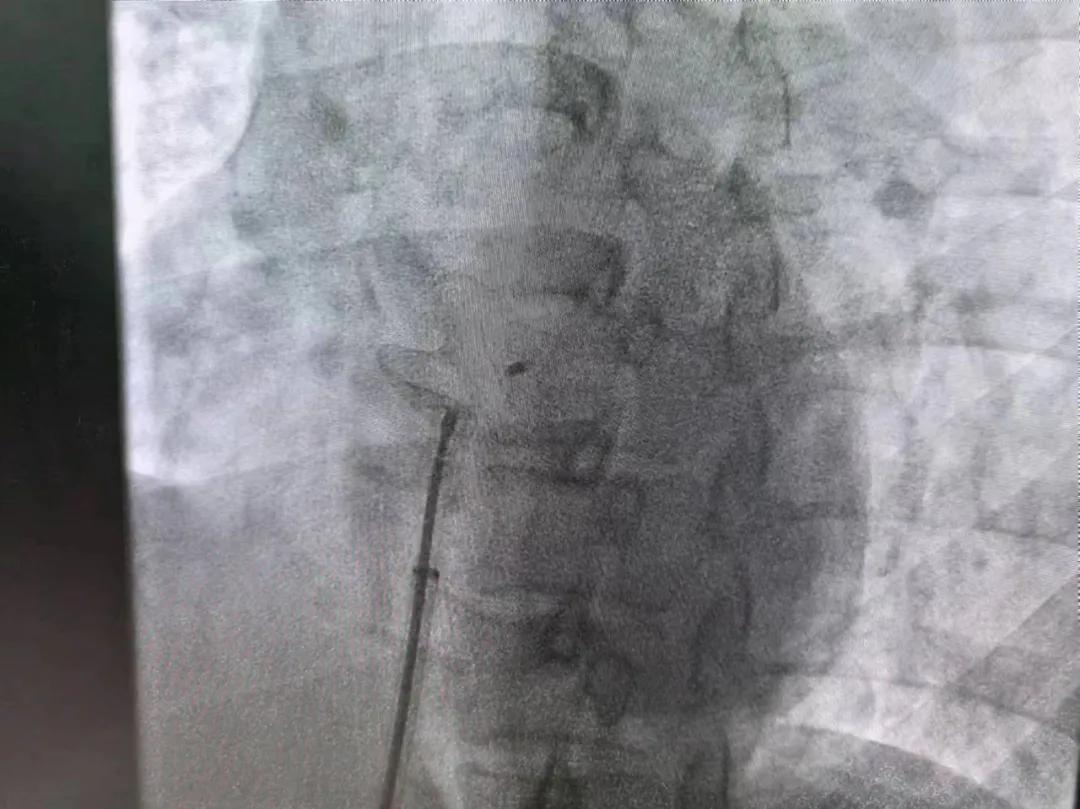

繼3月14日市二院成功開(kāi)展首例卵圓孔未閉介入封堵術(shù)之后,3月21日上午,市二院院長(zhǎng)王瑾及心血管內(nèi)科主任李慧新帶領(lǐng)心血管內(nèi)科介入團(tuán)隊(duì),再次成功為患者實(shí)施“經(jīng)皮房間隔缺損封堵術(shù)”,手術(shù)過(guò)程順利。該例病人的成功手術(shù)及康復(fù),標(biāo)志著市二院心血管內(nèi)科在結(jié)構(gòu)性心臟病介入診療中再次達(dá)到了新高度。

患者為中年女性,41歲,近2年一直反復(fù)出現(xiàn)頭暈、頭痛,曾先后在多家醫(yī)院就診。近期患者癥狀加重,出現(xiàn)活動(dòng)后氣喘合并胸悶癥狀,來(lái)到心血管內(nèi)科就診。經(jīng)心臟彩超檢查顯示:患者房間隔下段連續(xù)性中斷,缺損直徑達(dá)到了13mm,肺動(dòng)脈壓已經(jīng)輕度增高,確診為房間隔缺損。

于是,院長(zhǎng)王瑾會(huì)診后,詳細(xì)詢問(wèn)患者病史,認(rèn)真分析臨床癥候群并準(zhǔn)確診斷,耐心做好患者及家屬病情告知和充分溝通。經(jīng)過(guò)完善的術(shù)前評(píng)估及準(zhǔn)備,心血管內(nèi)科介入團(tuán)隊(duì)成功為患者實(shí)施“經(jīng)皮房間隔缺損封堵術(shù)”,手術(shù)過(guò)程順利。近日,患者已順利康復(fù)出院。 (尹紅婭 潘長(zhǎng)林)